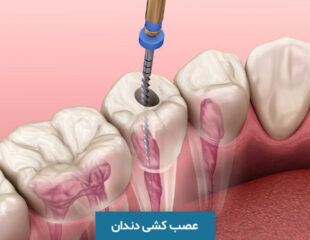

درمان ریشه دندان (عصب کشی) چگونه انجام می شود؟

هر دندان از قسمت های مختلفی تشکیل شده است که یکی از مهم ترین این بخش ها، ریشه دندان (root) ...

عصب کشی دندان چیست؟ هزینه عصب کشی چقدر است؟

عصب کشی دندان یا روت کانال (Root Canal) یک پروسه دندانپزشکی است که شامل از بین بردن بخش داخلی و ...